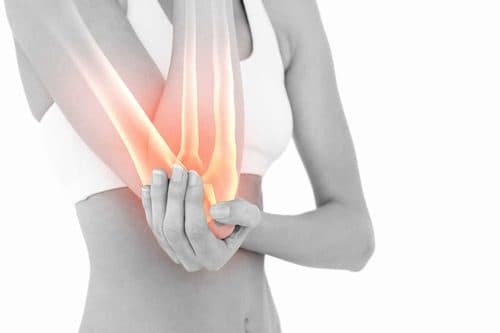

Hội chứng ống cổ tay  – nguyên nhân và cách điều trị

Hội chứng ống cổ tay là một bệnh lý phổ biến, có thể gặp ở mọi lứa tuổi tuy nhiên gặp nhiều nhất ở người từ 45-60. Tỷ lệ mắc bệnh ở nữ gấp 3 lần nam giới. Vậy nguyên nhân nào dẫn đến hội chứng ống cổ tay, triệu chứng bệnh như thế nào? […]